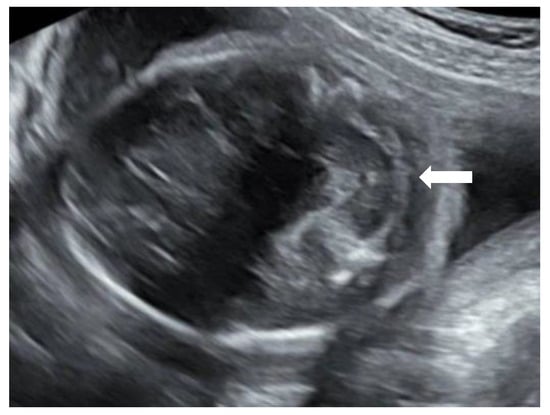

Figure 1), but no distinct banana-sign. Inspection of the spine was inconspicuous. The patient was reevaluated in our center at 24 weeks GA. The hydronephrosis of the upper pole of the left kidney remained stable. However, the cerebellum presented a banana-shape with herniation of the hindbrain onto C2 and minimal lemon-sign of the skull (

Figure 2). The lateral ventricles were not dilated. Ultrasound examination of the spine revealed a closed skin except for a minimal fistula in the sacro-coccygeal region (